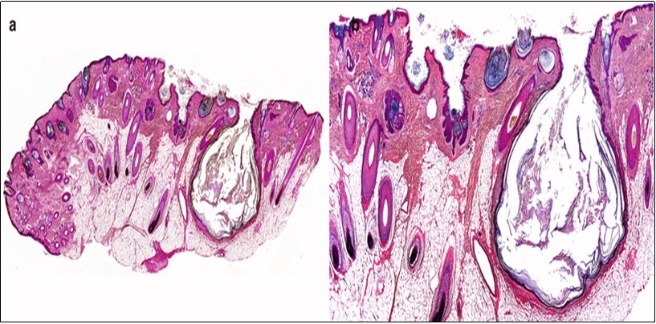

A cogent tissue specimen demonstrates typical features of comedones as follicular ostia distended and impacted with keratin. Significant histological manifestations are the occurrence of enlarged, grouped, distended follicular ostia demonstrating an absence of hair shafts along with impaction of laminated keratin. Base of the follicular invaginations may or may not delineate singular, rudimentary glandular structures. Miniature cysts, cystic invaginations and occasional enlarged cysts can be encountered. Cystic articulations are diverse and preponderantly layered by keratinizing, stratified squamous epithelium. Hyperkeratosis or epidermolytic hyperkeratosis and acanthosis of superimposed epidermis can concur although the lesion is devoid of parakeratosis or dyskeratosis5, 6.

Nevus comedonicus demonstrates immune reactivity to cytokeratin, simulating the expression of normal cutaneous surfaces. Generally encountered within the granular epidermal layer, immune reactivity for filaggrin is demonstrable within the entire epidermal thickness of closed comedones, a molecular which can be implicated in the genesis of nevus comedonicus6, 7. Electron microscopy demonstrates an enhanced quantification of Langerhans cells, numerous kerato-hyaline granules along with an abundance of tonofilaments within upper portion of stratum spinosum. Incompletely differentiated arrector pili muscles are impacted with intracellular glycogen particles6, 7. Figure 1, Figure 2, Figure 3, Figure 4, Figure 5, Figure 6, Figure 7, Figure 8, Figure 9, Figure 10.

Figure 9.Nevus comedonicus exemplifying a dilated, plugged follicular ostium, keratinous flakes and a layer of stratified squamous epithelium17.

Figure 10.Nevus comedonicus depicting an impacted, distended follicular ostium, keratinous aggregation and a superimposed, acanthotic, hyperkeratotic, stratified squamous epithelium17.